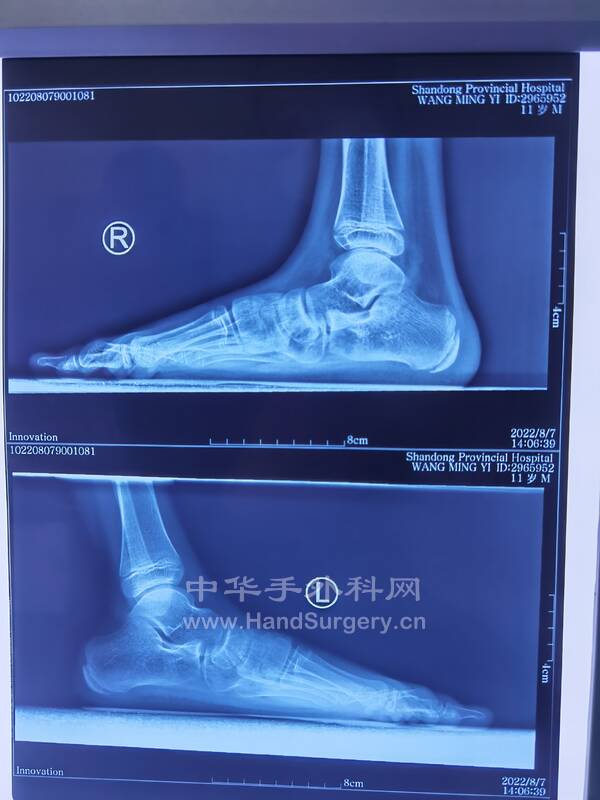

11岁男孩,双足扁平足,在老师这里见过的比较严重的孩子,老师建议手术治疗!

IMG_20220807_152904.jpg

IMG_20220807_152839.jpg

IMG_20220807_112458.jpg

IMG_20220807_152910.jpg